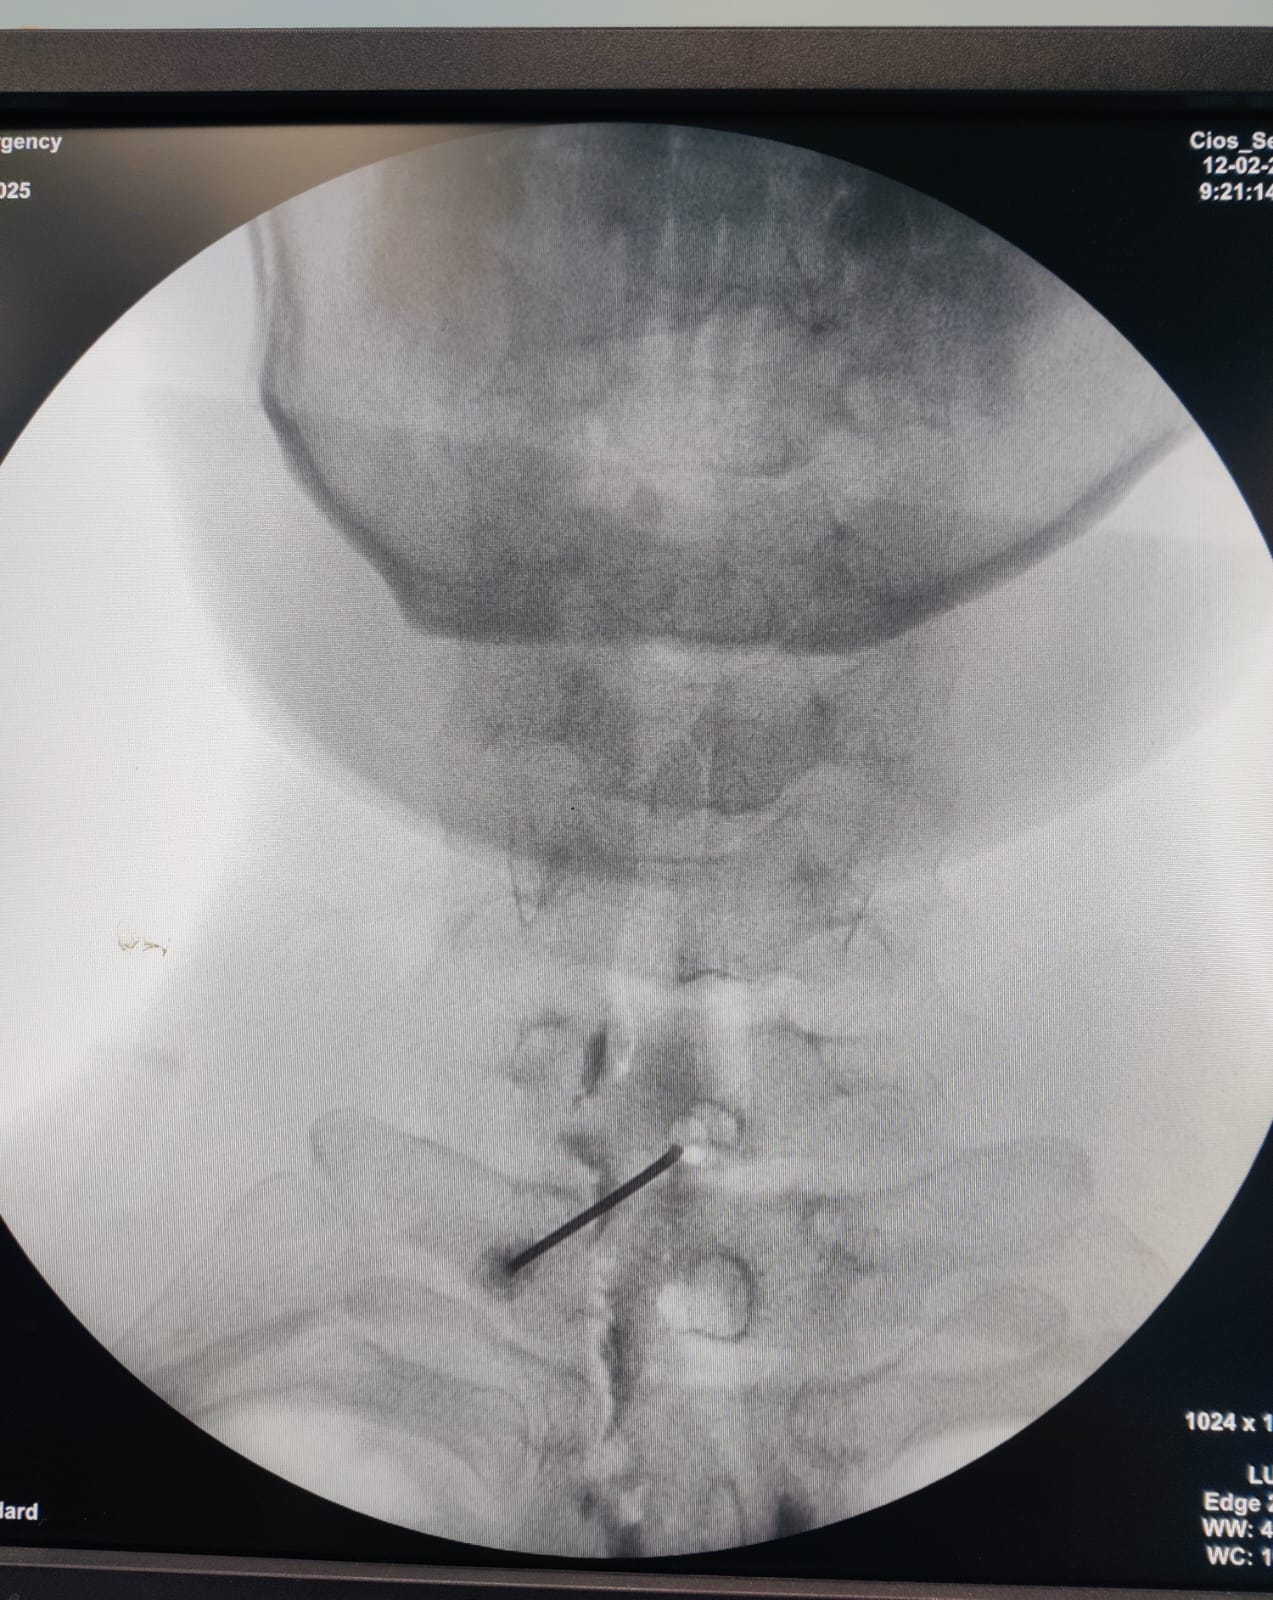

When to Consider a Cervical Epidural Injection? Cervical epidural steroid injections are an effective treatment option for patients suffering from chronic neck pain, cervical radiculopathy, disc herniation, and spinal stenosis. This procedure is particularly beneficial for individuals experiencing persistent neck pain radiating to the arms, tingling, numbness, or weakness due to nerve compression. 👉 Dr. Priya Rathi, the best spine and pain specialist, is an expert in performing cervical epidural injections with precision and care. She ensures optimal pain relief by combining this procedure with USG-guided dry needling to address the muscular component, providing long-term results. If you are struggling with chronic neck pain, consult Dr. Priya Rathi for a comprehensive and advanced pain management approach! ✅